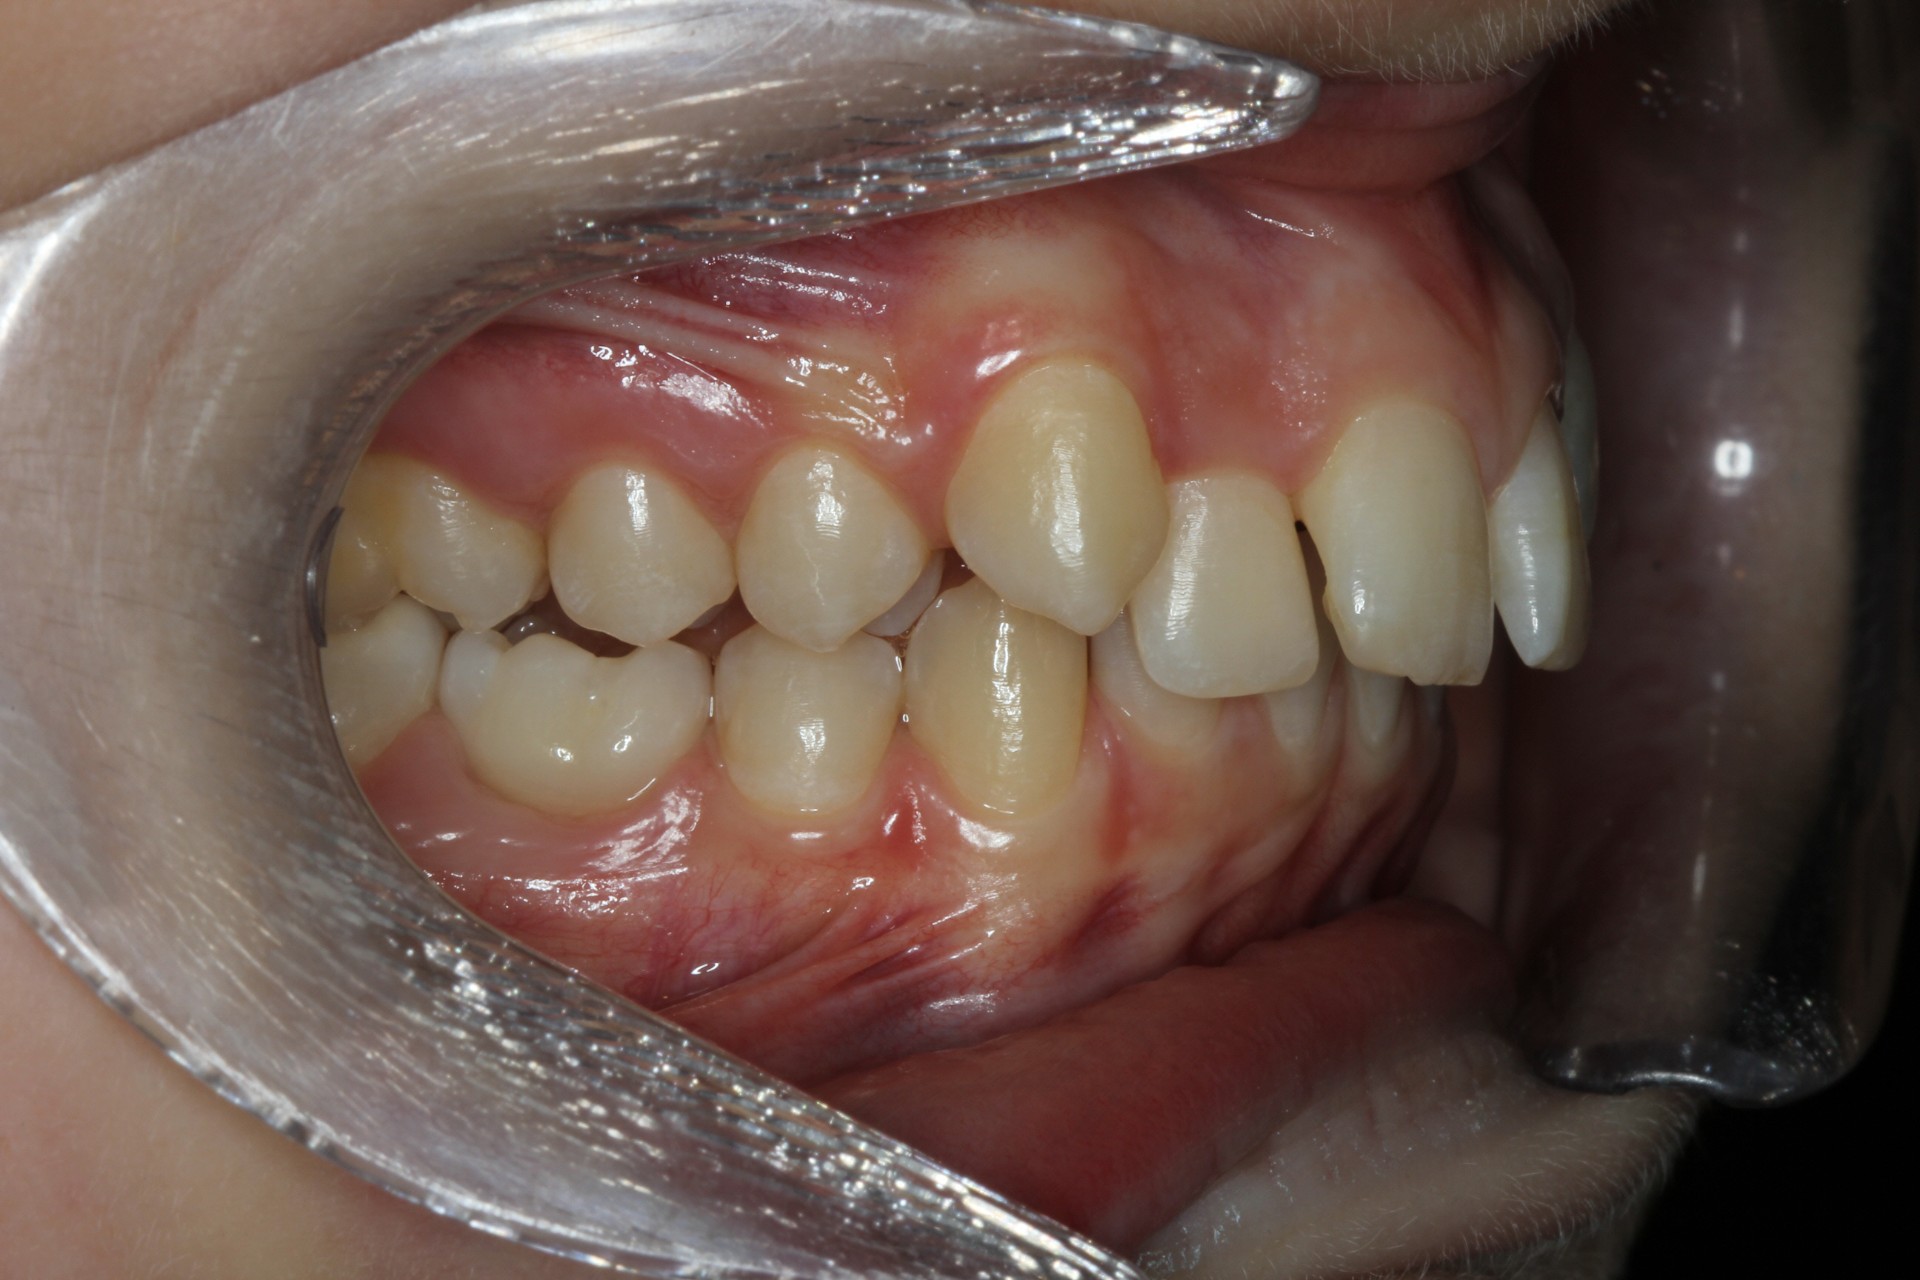

Protruding front teeth – Child case